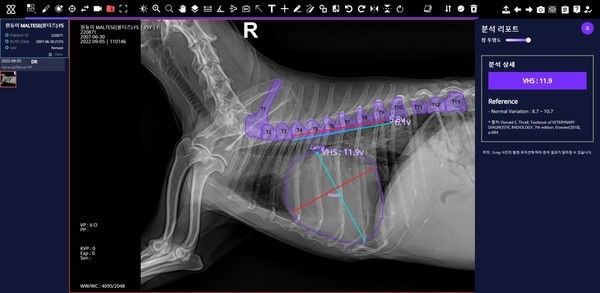

▲ 오이세 스카이동물메디컬센터 원장이 진료실에서 ‘엑스칼리버’를 통해 분석한 반려견의 엑스레이 사진을 설명하고 있다. 사진= SK텔레콤. |

수의사가 엑스레이 사진을 엑스칼리버에 올리면, AI가 부위별로 이상 여부를 분석해 결과를 제시한다. 이전에는 반려견 심장 크기를 측정하고 흉부 질환을 진단하려면 기존에는 수의사가 흉추를 기점으로 엑스레이에서 길이를 측정해 심장 위치를 파악하는 과정을 거쳤다.

질환탐지율도 상당히 높다는 게 SK텔레콤의 설명이다. 반려견 근골격 이상 영역 7종 검출모델 평균 질환탐지율은 86%, 반려견 흉부 이상 패턴 10종 분류모델 평균 질환탐지률은 84%에 달했다. 반려견 심장크기측정(VHS) 측정의 경우, 정확도가 97%나 됐다. 관계자는 데일리임팩트에 “AI의 질환탐지율은 분야별로 84~97% 수준에 달한다”며 ”학습데이터가 늘어날수록 AI 성능이 향상되므로, 엑스칼리버의 품질도 올라갈 것으로 본다”고 전했다. 이와 관련, 제주대가 최근 엑스칼리버 개발에 합류했다.

| ▲ 엑스칼리버를 통해 분석한 반려견의 근골격·흉부·VHS 엑스레이. 사진= SK텔레콤. |